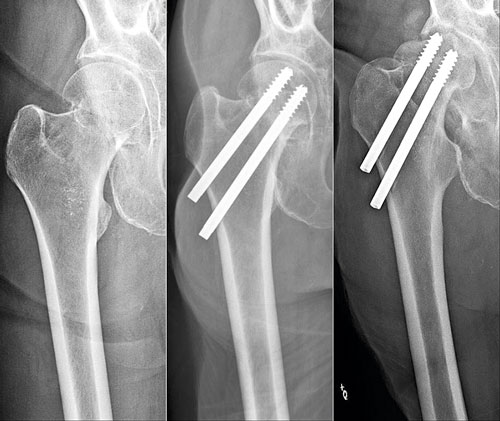

Vid odislokerad cervikal fraktur finns god chans för läkning vid operation med endast osteosyntesmaterial, varför dessa i majoriteten av fallen opereras med två parallella skruvar eller krokförsedda spikar genom collum.

Cervikal höftfraktur hos 69-årig patient som halkat, opererad med skruvar. 2 år senare sökte han primärvården med smärta i höftleden. Röntgen visade caputnekros och skruvpenetration. Patienten remitterades till ortopedklinik och planerades för reoperation med extraktion av skruvar samt helprotes.

Till vänster en icke-opererad pertrokantär fraktur och till höger en som är opererad med glidskruv och platta. God reposition är mycket viktig för frakturläkningen.

Haveri av osteosyntesmaterial. Till vänster: Patient med en initialt odislokerad cervikal höftfraktur. Patienten besvärades sedan operationen av värk i ljumsken och lateralt kring höften. Värken blev så pass uttalad att den störde nattsömnen. På slätröntgen sågs icke-läkning i frakturen, och den kaudala skruven hade backat och stack ut i mjukdelarna. Till höger: Patient med subtrokantär femurfraktur som opererats med lång märgspik. Patienten hade smärta och stelhet i höften och värk i framför allt ljumsken. Initialt var patienten nöjd med sin höft men hade fått mer och mer ont de senaste månaderna och hade svårt att promenera till närmaste affären. Osteosyntesmaterialet hade migrerat kraniellt, och kollumskruven hade skurit ut genom caput och penetrerade leden.